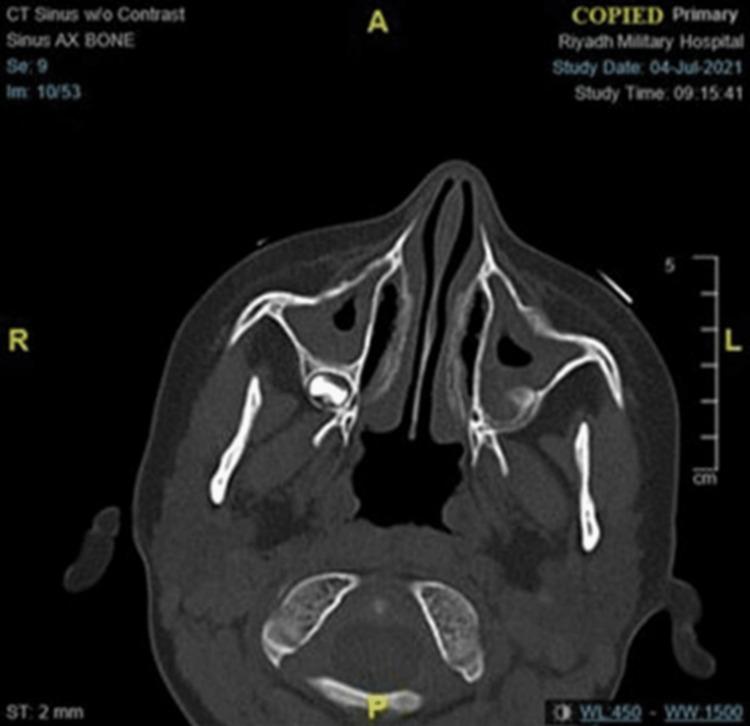

Primary ciliary dyskinesia (PCD) is a rare autosomal recessive inherited heterogeneous respiratory disorder. The diagnosis of PCD is challenging and necessitates a multi-test diagnostic approach because there are no gold standard diagnostic tests available to confirm PCD. However, rapid advancement in understanding the molecular genetic basis of PCD has greatly improved PCD diagnosis. Studies have reported that PCD may increase the risk of rheumatoid arthritis, congenital heart disease, severe esophageal diseases, and others. Therefore, the present study aimed to assess the risk of type 1 diabetes mellitus (T1DM) in a genetically confirmed PCD patient. In this case study, an 11-year-old girl with autosinopulmonary infections and her younger brother were diagnosed with PCD. The patient's DNA was extracted for next-generation exome sequencing. Our analysis of the exome sequencing data revealed the PCD-causing genetic variant p.Glu286del in the RSPH9 gene on chromosome 6p21.1. In addition, the biochemical findings at the time of patient's admission showed elevated glutamic acid decarboxylase antibodies, HbA1c, and ketone levels, with impaired glucose tolerance, which indicated the presence of T1DM. In conclusion, the clinical features, biochemical reports, and genetic testing confirmed PCD in this patient and the possible association between PCD and T1DM.

原发性纤毛运动障碍(PCD)是一种罕见的常染色体隐性遗传性异质性呼吸系统疾病。PCD的诊断具有挑战性,需要采用多种检测的诊断方法,因为目前尚无金标准诊断测试来确诊PCD。然而,在理解PCD分子遗传基础方面的快速进展极大地改善了PCD的诊断。研究报告称,PCD可能会增加类风湿性关节炎、先天性心脏病、严重食管疾病等的发病风险。因此,本研究旨在评估经基因确诊的PCD患者患1型糖尿病(T1DM)的风险。在本病例研究中,一名患有自限性肺部感染的11岁女孩及其弟弟被诊断为PCD。提取了该患者的DNA用于下一代外显子组测序。我们对外显子组测序数据的分析揭示了位于6号染色体p21.1上的RSPH9基因中导致PCD的基因变异p.Glu286del。此外,患者入院时的生化检查结果显示谷氨酸脱羧酶抗体、糖化血红蛋白(HbA1c)和酮体水平升高,葡萄糖耐量受损,这表明存在T1DM。总之,临床特征、生化报告和基因检测证实了该患者患有PCD以及PCD与T1DM之间可能存在的关联。